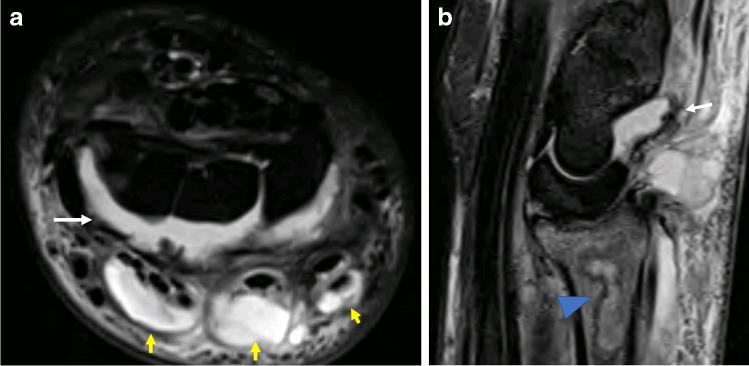

Complications in musculoskeletal interventions are rare and where they do occur tend to be minor, and often short-lived or self-limiting. Nonetheless, the potential for significant complications exists, and a thorough understanding of both the mechanisms which contribute and the manner in which they may clinically present is of critical importance for all musculoskeletal radiologists involved in performing procedures, both to mitigate against the occurrence of complications and to aid rapid recognition. The purpose of this review is to analyse the relevant literature to establish the frequency with which complications occur following musculoskeletal intervention. Furthermore, we highlight some of the more commonly discussed and feared complications in musculoskeletal intervention, such as the risk of infection, potential deleterious articular consequences including accelerated joint destruction and the poorly understood and often underestimated systemic effects of locally injected corticosteroids. We also consider both extremely rare but emergent scenarios such as anaphylactic reactions to medications, and much more common but less significant complications such as post-procedural pain. We suggest that meticulous attention to detail including strict adherence to aseptic technique and precise needle placement may reduce the frequency with which complications occur.